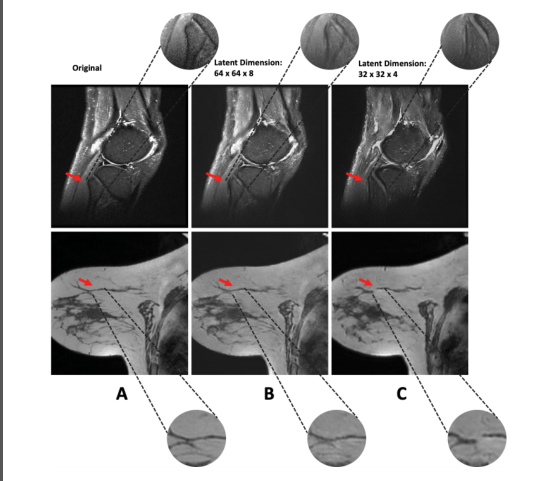

为了分析潜在维度对图像生成质量的影响,我们使用两种不同的压缩因子训练VQ-GAN自动编码器。我们发现,当将每个空间维度压缩8倍(即,256x256x32大小的图像的潜在维度为32x32x4)时,相关的解剖特征会丢失(图3)。当使用较小的压缩因子4训练VQ-GAN自动编码器时(即,尺寸为256x256x32的图像具有64x64x8的潜在尺寸),解剖特征被更精确地重建。对于所有四个数据集,我们发现最大压缩因子4(即,与图像的原始维度相比,潜在空间中的每个维度都小了四倍)包含了正确的解剖细节,如放射学专家在每个数据集的20个样本图像的测试集中所评估的。